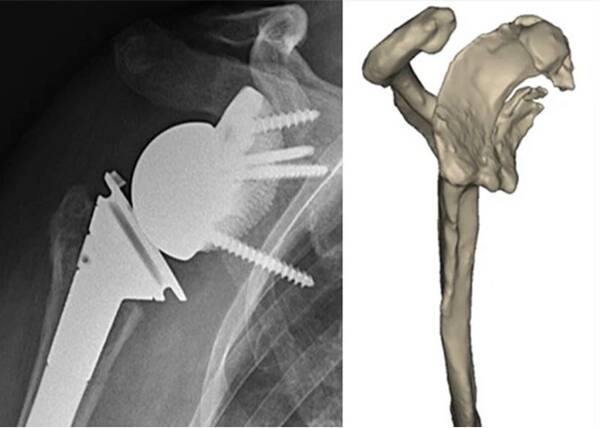

△在該病例中醫(yī)生發(fā)現(xiàn)患者患有嚴(yán)重的肩關(guān)節(jié)退行性疾病,且肩盂頂部完全缺失,因此決定在此案例中不使用傳統(tǒng)的倒置全肩關(guān)節(jié)固定基板

Materialise公司表示,它們有一位名叫Mr. Terwiel的患者需要進(jìn)行肩關(guān)節(jié)置換手術(shù)。由于該名患者的病情十分嚴(yán)重,傳統(tǒng)的假體可能無(wú)法為他提供足夠的支持和穩(wěn)定性。因此,醫(yī)生選擇了使用該公司的的個(gè)性化植入物Glenius來(lái)為她定制肩關(guān)節(jié)假體。

該公司的臨床工程師通過(guò)使用患者的CT掃描數(shù)據(jù)和3D技術(shù),為她設(shè)計(jì)了一個(gè)定制的肩關(guān)節(jié)假體,并且為醫(yī)生提供了一個(gè)3D打印的手術(shù)指南,以幫助他們更好地安裝這個(gè)假體。手術(shù)成功完成后,Mr. Terwiel恢復(fù)得很好,現(xiàn)在已經(jīng)可以進(jìn)行各種肩膀活動(dòng)了。這個(gè)案例展示了Materialise個(gè)性化植入物技術(shù)的效果,并證明了它可以為患者提供更好的治療效果。